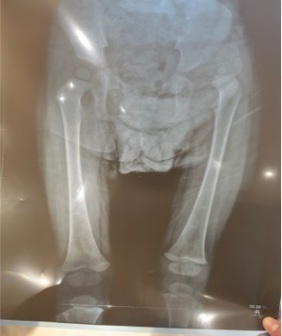

了解到小卓嘎的情况后,李玉希主治医师对她进行了详细的体格检查,初步判断其可能为“发育性髋关节脱位”。随后的骨盆X光证实,白玛卓嘎左侧髋臼发育不良,股骨头已经脱出髋臼。

X线片显示患儿左侧先天性髋关节发育不良,股骨头脱位,Allis征(+)